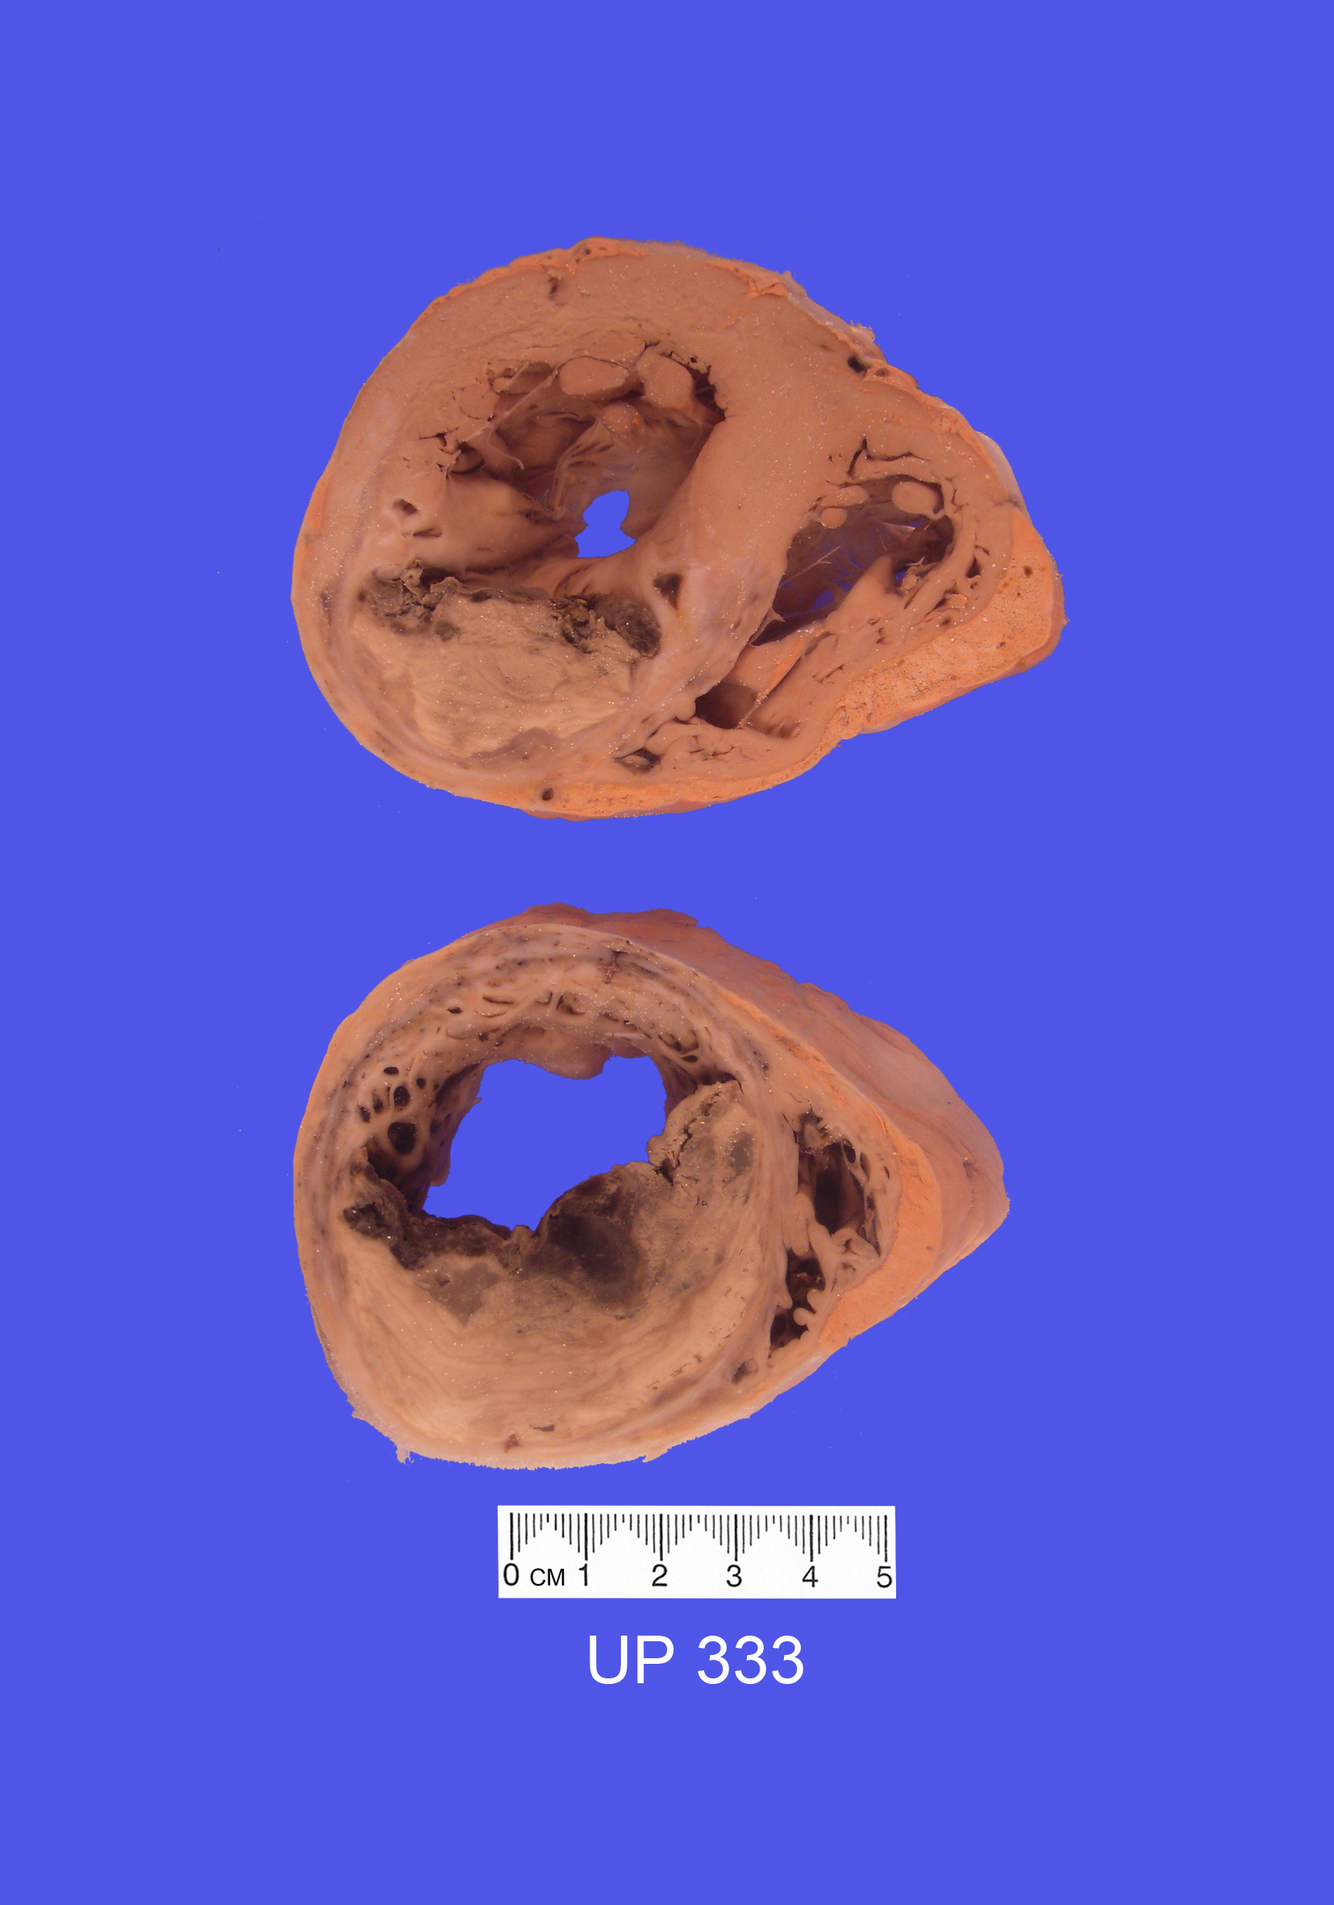

The mounted specimen shows two transverse slices through the heart. There is an extensive anteroseptal myocardial infarct. Geographic zones of pale yellow necrotic cardiac muscle (coagulative necrosis) are present edged by congested, translucent grey tissue (granulation tissue). This infarct involves the full thickness of the myocardium at the apex.

The visceral pericardium is intensely congested and covered by a fibrinous exudate, consistent with the friction rub detected clinically. Adherent apical mural thrombus is present. The left ventricle is also markedly hypertrophied.